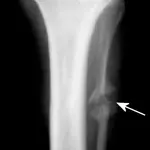

Figure 3A. This series represents an example of a probable fracture that cannot be seen on routine radiographs but that produces secondary signs that can be seen. Slight thickening of the caudal cortex of the tibia (arrow) is present in a dog with left hind limb lameness. The dog is an active, 3-yearold, castrated male black Labrador retriever having lameness for several months but with no prior history of lameness.

Figure 3B. Lameness was persistent, and cortical thickness progressed (arrow) over a 4-month period. Panosteitis might be considered in the differential diagnosis because of the several areas of uptake, although panosteitis does not typically start as a focal unicortical thickening of the bone in a 3-year-old dog.